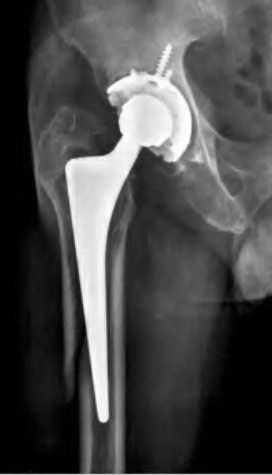

A 75-year-old man underwent total hip arthroplasty 10 years ago. He now reports mild groin pain which has been increasing lately. What is the most likely explanation for the finding in Figure A indicated with the arrows?

Osteolysis of the pelvis is a common complication associated with total hip arthroplasty. Osteolysis affects sockets with and without cement, and has been attributed to the biologic reaction to wear debris. With well-fixed cementless sockets, an expansile pattern of osteolysis is usually seen.

The radiographic appearance has a radiolucent area that starts at the implant-bone interface and expands into the cancellous bone away from the implant.

This pattern of osteolysis can be explained with the concept of effective joint space. This concept states that joint fluid and wear particles will flow according to pressure gradients and follow the path of least resistance.

The Level 5 review article by Chiang discusses osteolysis in further depth.